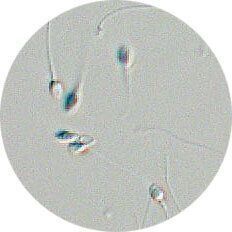

●問診・触診・精液検査

初診は婦人科、問題があれば泌尿器科へ。睾丸の発育状況、性器の奇形、精索静脈瘤などを視診・触診し、精液検査を行います。数日間禁欲後、自宅か病院でマスターベーションをし、精液を2時間以内に病院に提出します。

★精液検査で調べること

精液検査では精液の量や精子の数、運動率、奇形率などを調べます。また酸性度が高いと感染症の疑いが。白血球や赤血球が多い場合は、炎症の可能性も。精子の運動率は複数回行って判断する場合も。